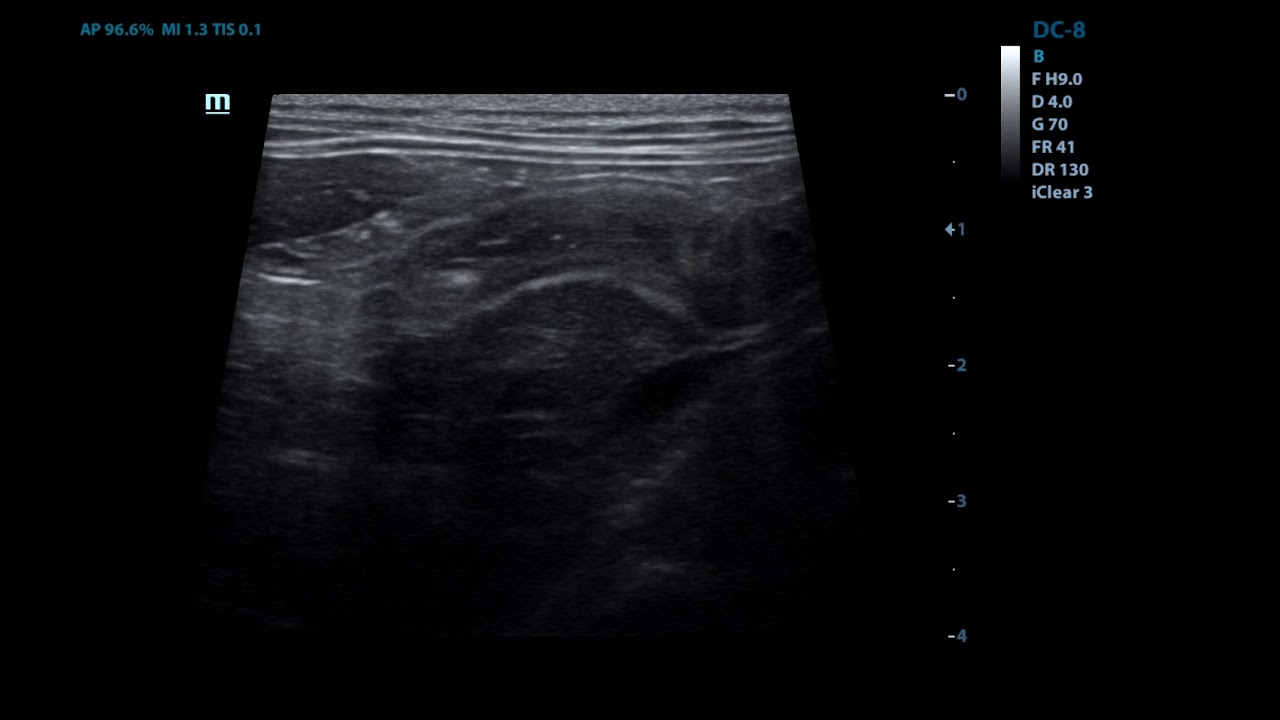

Если вы подозреваете (или знаете наверняка), что собака проглотила что-то несъедобное, немедленно свяжитесь с ветеринарной клиникой и до врачебного осмотра не позволяйте животному ничего есть и пить. Доктор проведет обследование, которое подтвердит или опровергнет ваши опасения. Диагноз ставится комплексно: клинические признаки, анамнез, наблюдения владельца и специальные методы исследования, такие как рентген, УЗИ, эндоскопия.

Дальнейшая диагностика происходит в условиях клиники. Осмотр доктора подтверждается результатами анализа и эндоскопическими исследованиями. В зависимости от того, какой предмет проглотила собака, его наличие и точное расположении можно установить с помощью рентгена или УЗИ. Лучшие метода диагностики и лечения обеспечит ветеринарная клиника АВВА.

- УЗИ – еще один способ обнаружения инородных тел. Позволяет выявить наличие непроходимости по механическим причинам. Если есть инородный предмет, и двигательные функции кишечника сохранены, организм собаки будет пытаться его вытолкнуть.

Аппарат УЗИ дает возможность зафиксировать маятникообразное перемещение посторонней вещи по кишке.

Инородное тело не всегда будет очевидным, и иногда рекомендуется исследование с контрастным веществом или барием, поскольку это может выделить инородное тело или выделить закупорку.Ультразвук брюшной полости также может быть полезен для оценки состояния живота и определения курса лечения.

Однако в большинстве случаев диагноз устанавливается с помощью рентгенограмм (рентгеновских снимков) кишечного тракта вашей собаки или ультразвукового исследования брюшной полости.

Твердый объект располагался в кишечнике в каудальном левом квадранте брюшной полости.Поскольку он перекрывал толстую кишку, не сразу было очевидно, находится ли объект в тонком или в толстом кишечнике. Мы провели ультразвуковое исследование его брюшной полости и обнаружили объект в тонкой кишке, на полпути между желудком и толстой кишкой.